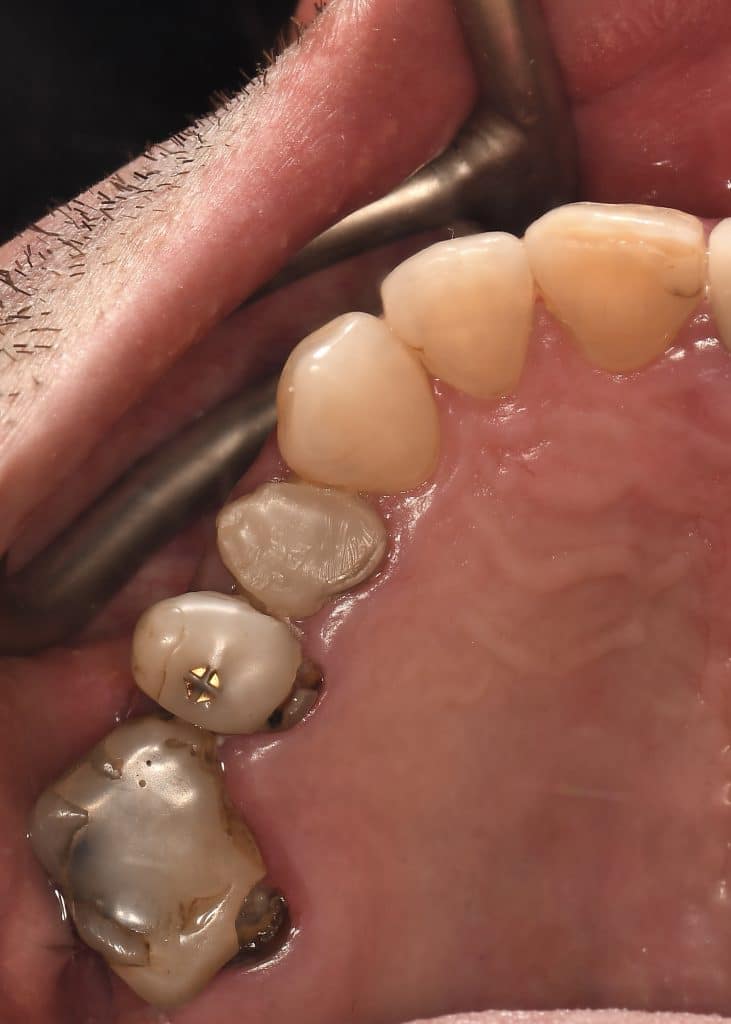

Case of the day where i extracted the 34-35-36 and an immediate placement of 2 implants in the 34-36 sites

sticky bone grafting GTO by osteobiol was used with straumann xenograft